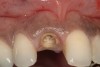

A 34-year-old woman presented with a chief complaint of mild discomfort and swelling associated with the maxillary left lateral incisor. The patient reported a history of root canal therapy and crown performed approximately 10 years earlier. Findings from the clinical examination revealed a localized buccal gingival swelling at the level of the mucogingival junction distal to the lateral incisor, with a 9-mm probing depth on the direct facial of the tooth (Figure 1 ). Observations from the radiographic examination demonstrated a periradicular radiolucency but suggested normal interdental bone levels (Figure 2 ). Surgical exposure following flap elevation exposed a 10-mm dehiscence defect of the buccal plate (Figure 3 ), which was consistent with a vertical root fracture and hopeless prognosis. The lateral incisor was extracted to minimize the loss of alveolar bone and this was followed by thorough degranulation of the socket. Particulate FDBA saturated with rhPDGF-BB for 10 minutes was then applied to augment the deficient ridge in preparation for future implant placement (Figure 4 ). The extraction site was developed to approximate the contours of the adjacent alveolar ridge. Then, a resorbable collagen membrane (Bio-Gide®, Osteohealth) was placed over the graft to facilitate graft containment and maintenance of desired alveolar contours (Figure 5 ). Placement of the membrane without disruption or displacement of the graft during completion of the surgical procedure and suturing is critical to ensure clot formation that will support bone formation.

Figure 2  Periapical radiograph of lateral incisor shows periradicular radiolucency but suggests normal interdental bone levels.

Figure 2